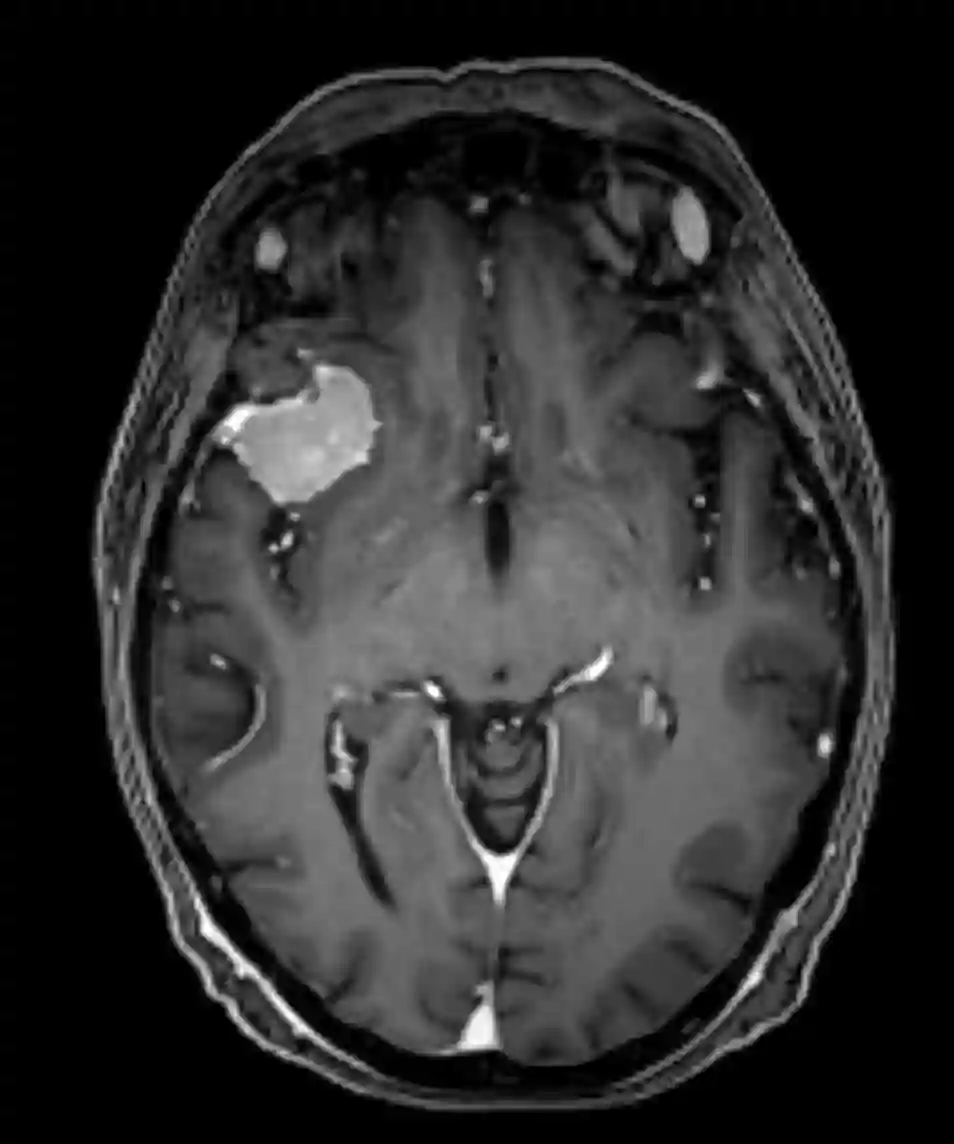

Bildgebung

Der Goldstandard in der Beurteilung von Keilbeinflügelmeningeomen ist die MR-Bildgebung, welche je nach Tumor durch eine CT-Bildgebung zur Beurteilung der ossären Strukturen ergänzt werden kann. In einzelnen Fällen kann eine zerebrale Angiographie indiziert sein, um gegebenenfalls eine präoperative Embolisierung der Gefäßversorgung des Tumors durchzuführen.